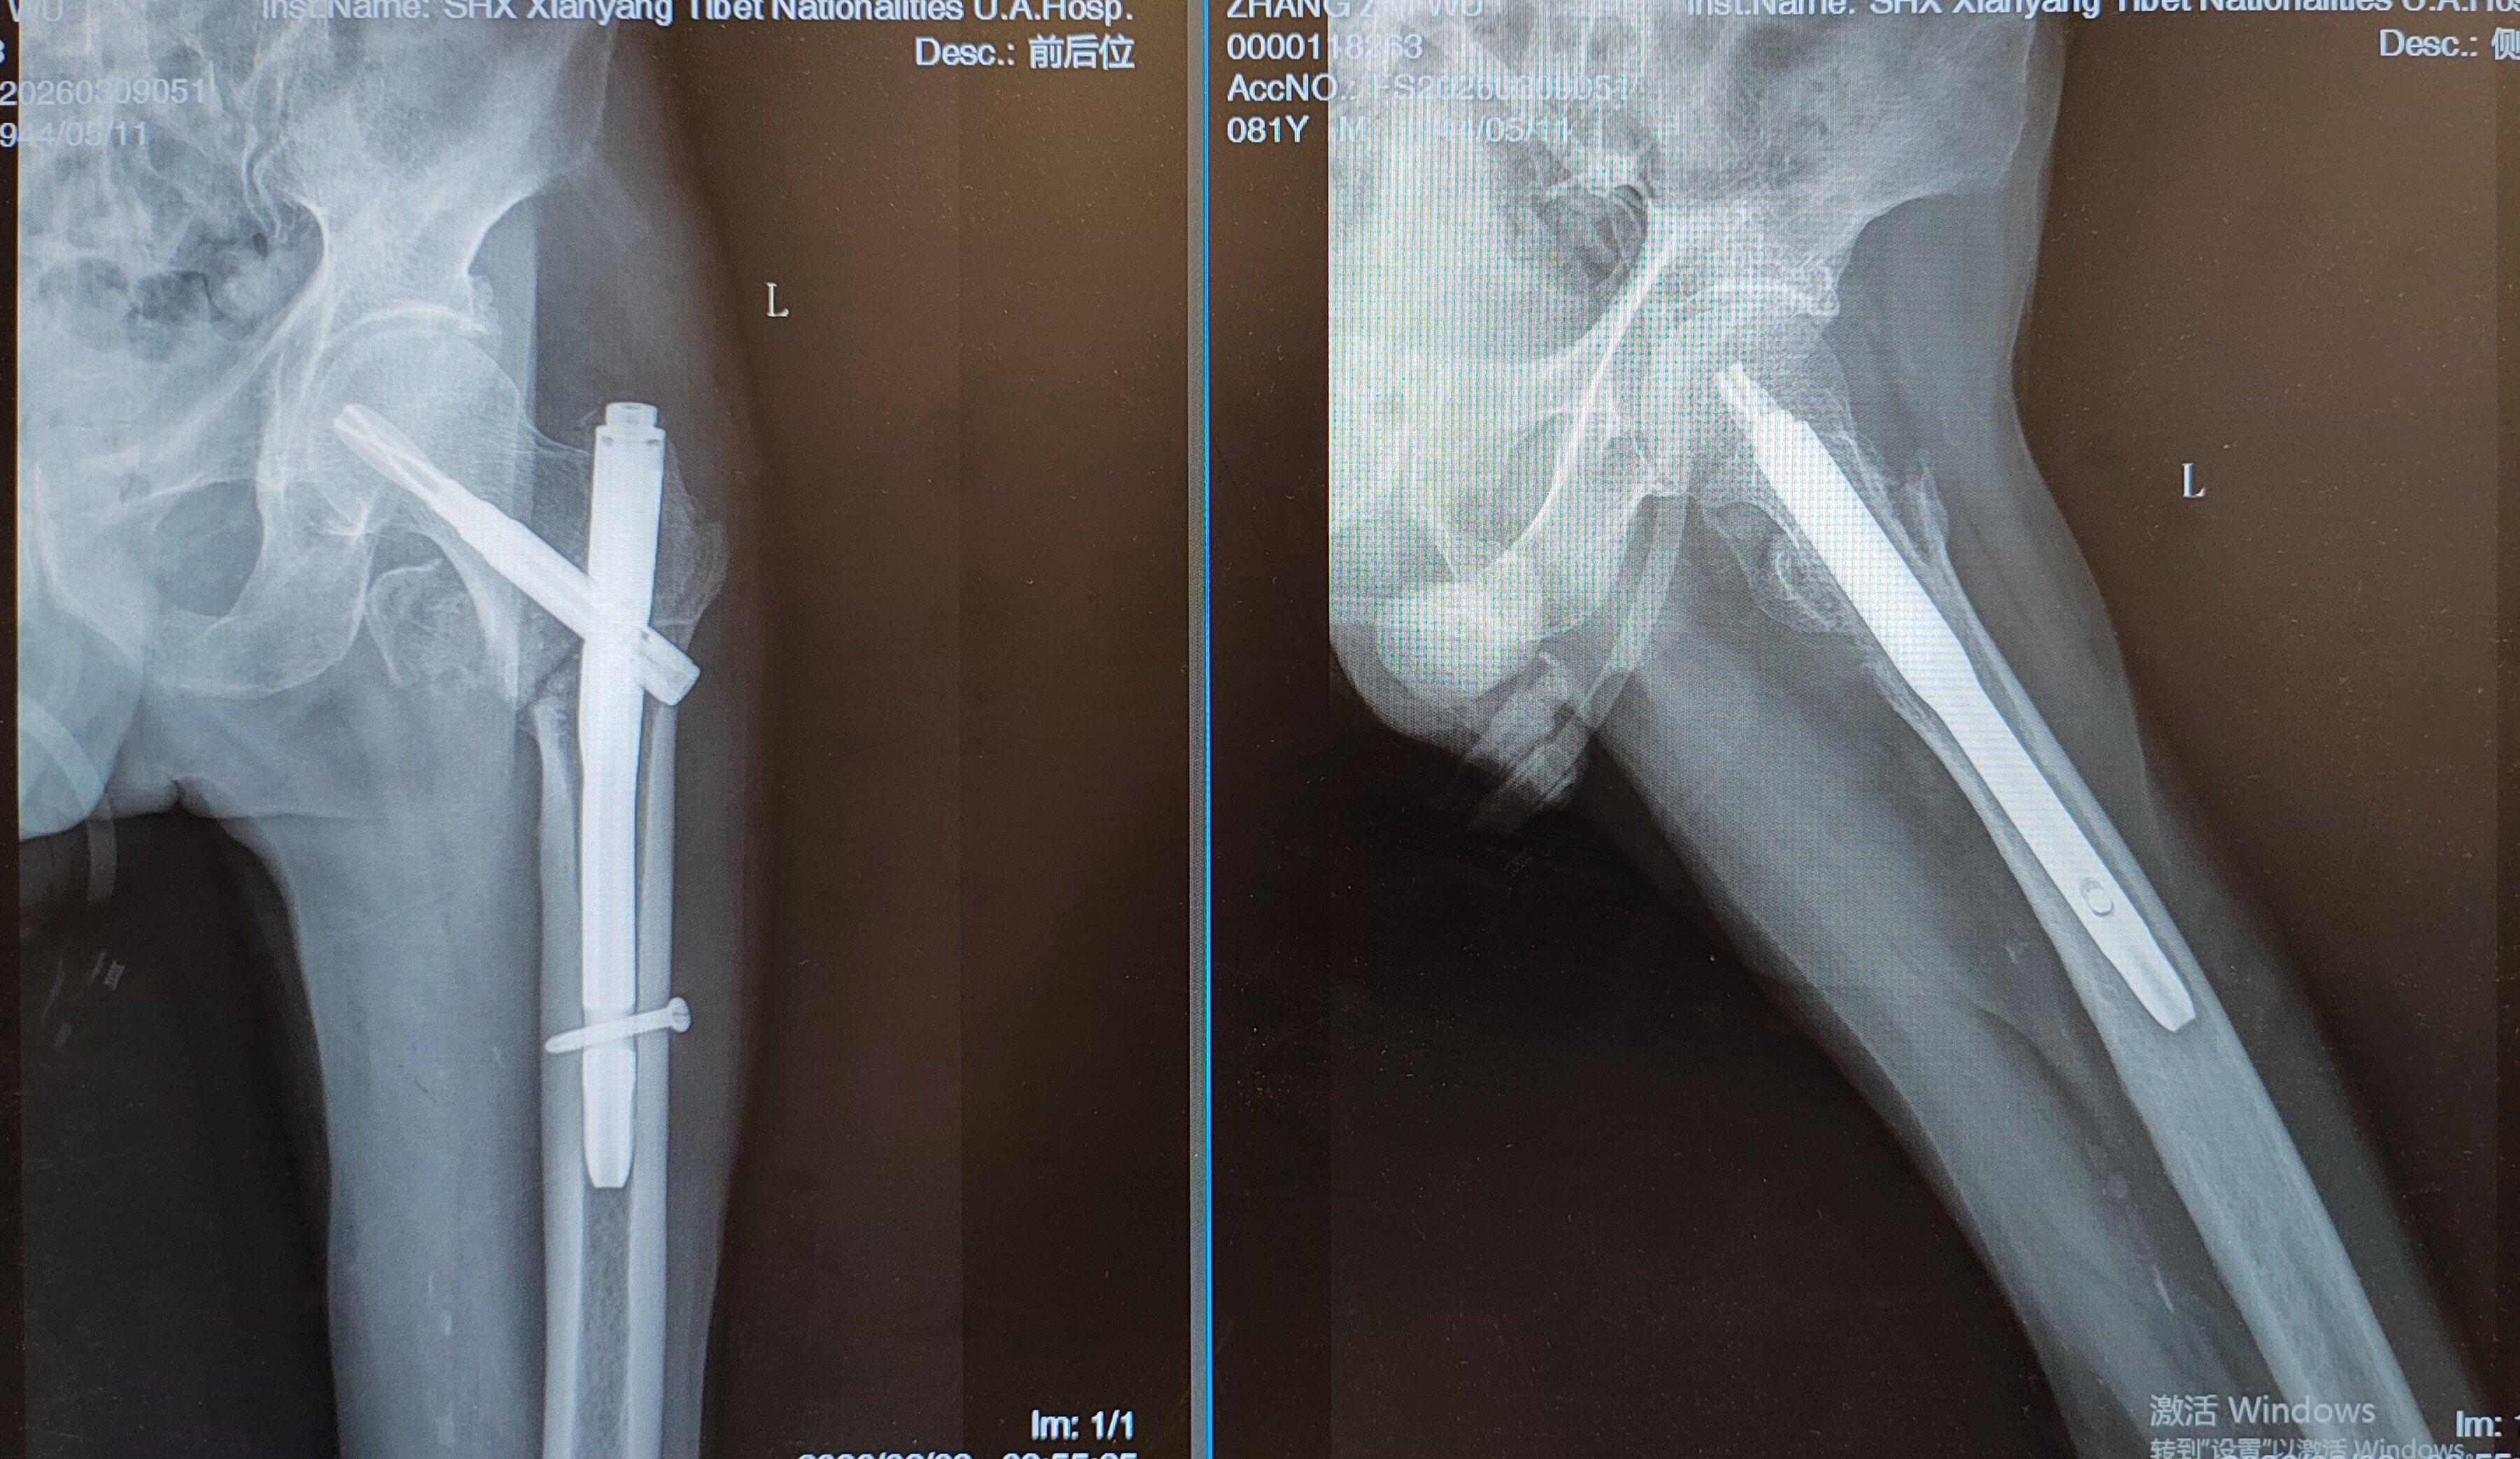

2月中旬,在麻醉手术部医护团队的紧密配合下,赵昕副主任医师为患者实施左股骨转子间骨折闭合复位微创切口髓内钉内固定术。该术式切口小、出血少、对机体干扰轻,最大限度降低了高龄患者手术创伤,契合快速康复理念,也是骨科针对老年髋部骨折的特色优势技术。手术过程顺利,术后患者生命体征平稳,相关化验指标基本稳定,手术取得圆满成功。

(术后为患者后续顺利恢复、早日实现站立行走打了下坚实基础)